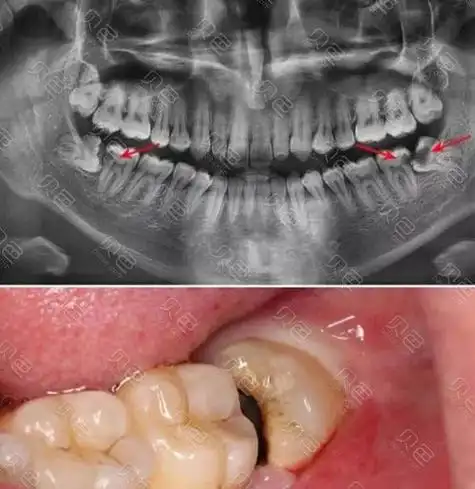

形态不一的下颌阻生智齿,不论啥形态反正都不在正常位置上~#口腔正畸

阻生智齿不同形态示意图